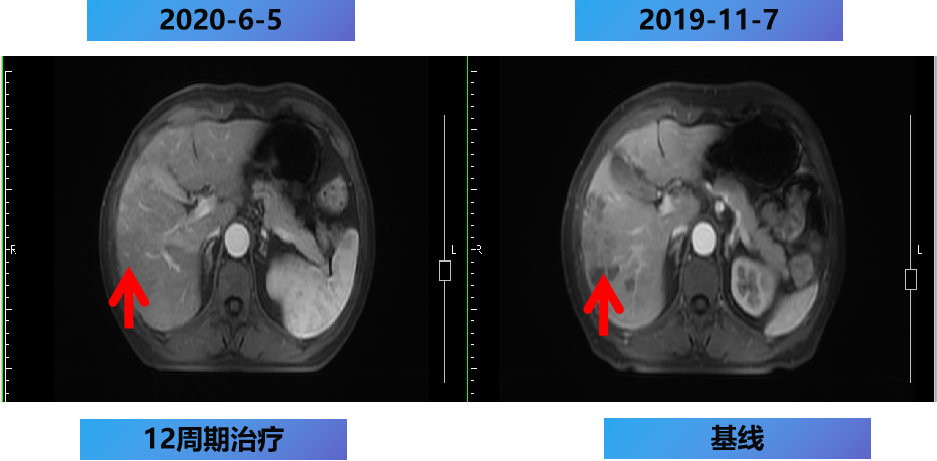

一线第1-12周期 CET+FOLFOX。

开始时间:2019-11-15至2020-5-2 每2周 一线治疗。

【治疗方案疗效评估】

MDT意见:肝转移灶可切除,肺转移灶缩小。

治疗目标:NED。

治疗策略:原发灶切除和肝转移灶切除,肺转移灶择期手术。